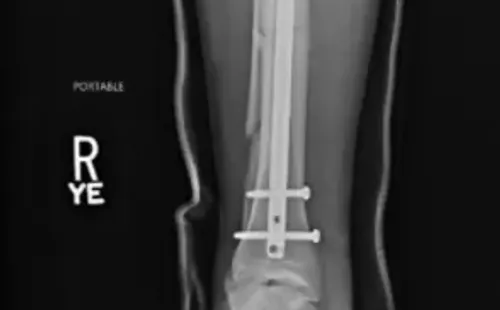

A través de su cuenta de Twitter, el artista marcial compartió imágenes del proceso que se llevó a cabo para reconstruir su pierna. En ellas se pueden ver la barra de titanio que se le dejó para afirmar sus huesos, además de los tres tornillos que fijaron la placa.

Weidman terminó con un fierro y tres tornillos. Foto: Twitter